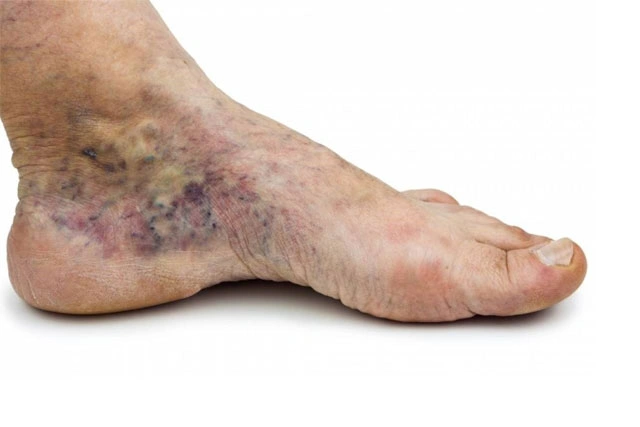

Pie diabético isquémico (problemas de circulación)

Síntomas de insuficiencia arterial (problemas de circulación)

• Pies fríos

• Perdida del vello

• Uñas gruesas y quebradizas

• Dolor en la pantorrilla al caminar (claudicación)

• Piel brillante

• Dolor de predominio en la noche

• Cambios de coloración en el pie o dedos (color negro o morado)

Acude a nuestra clínica somos especialistas en enfermedades circulatorias